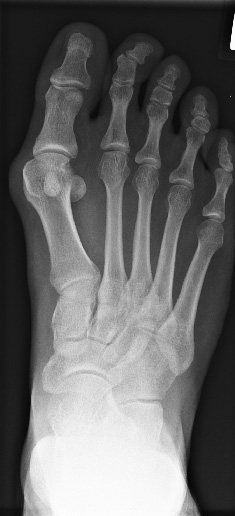

- Umstellung bei Hallux valgus, Gelenkerhaltend, wenn möglich (Abb. 9)